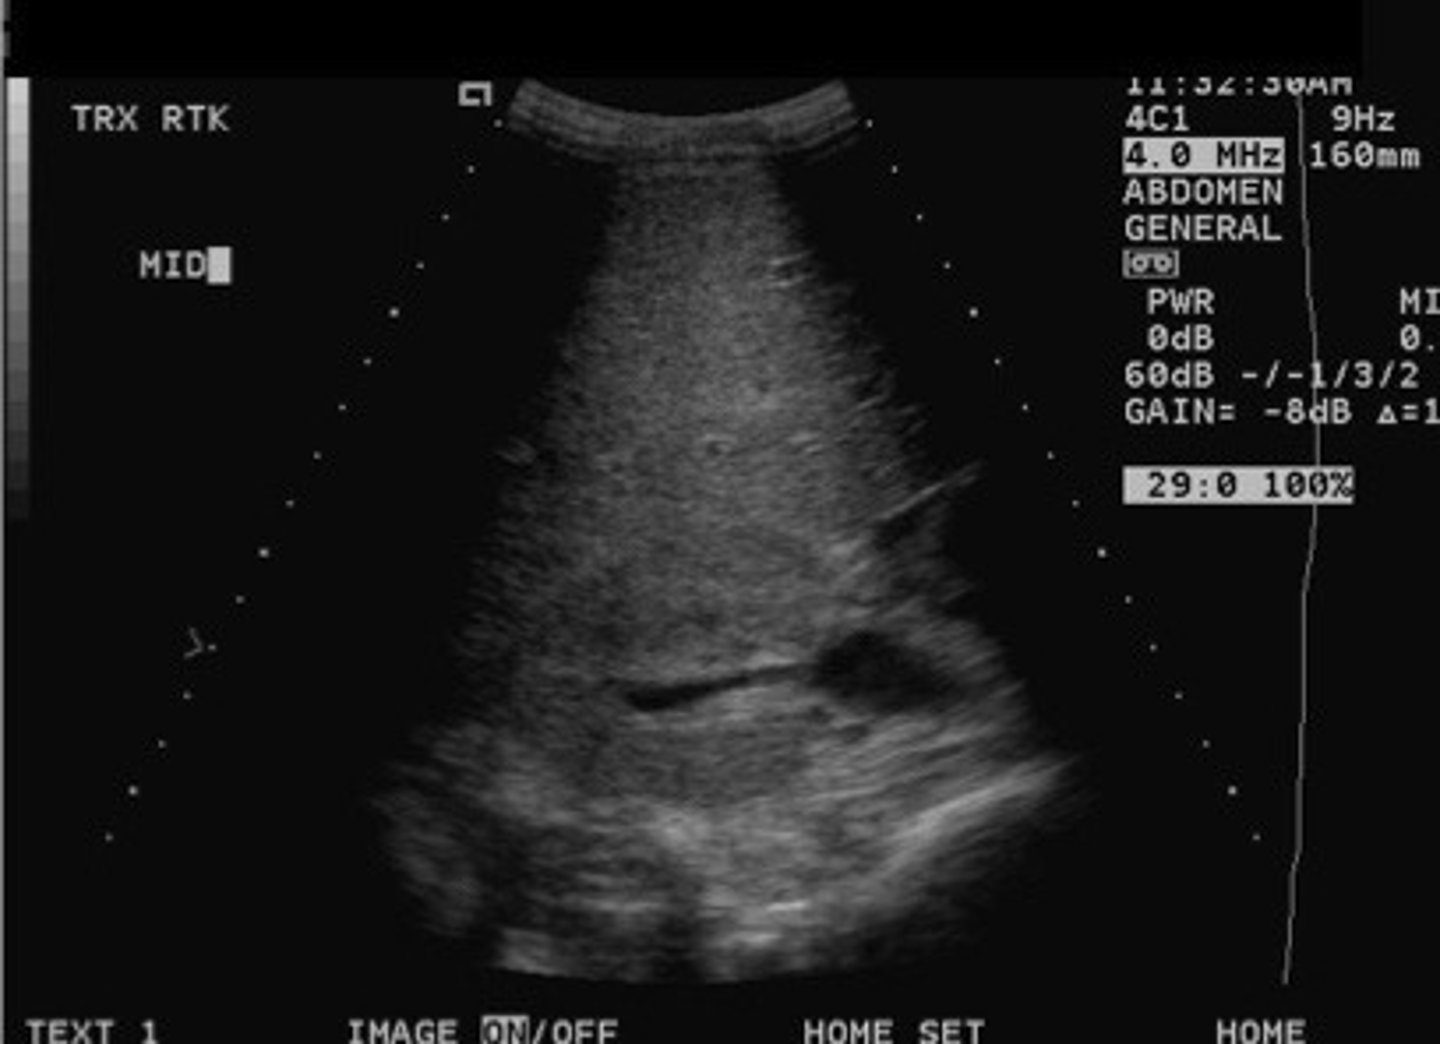

Stone difficult to identify in the sinus region

What does this image show

Stone now identified with the twinkle artifact